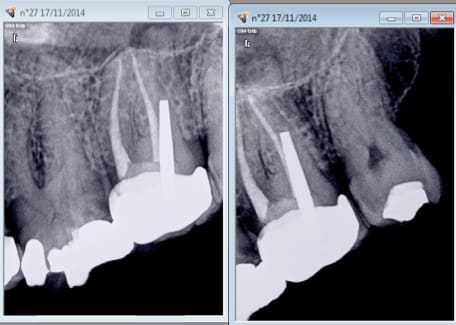

Ca c'est un ic coiffe protilab, pourquoi ca a merdé au bout de 7 ans à ton avis ? -)

parce que le pivot ne va pas a l'apex

pas de pivot jusqu'a l'apex